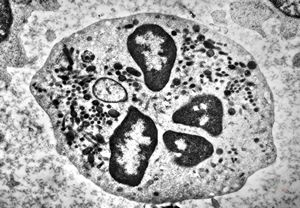

blood - neutrophilic granulocyte

F,61y. | blood - neutrophilic granulocyte